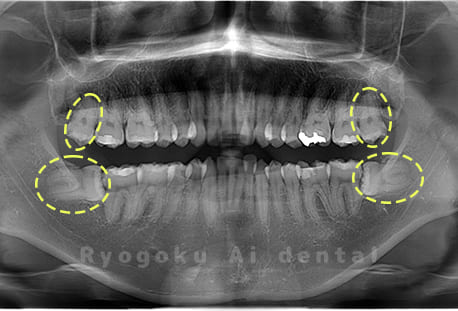

Case04

- 原因

- 上顎の親知らず、下顎の水平埋伏の親知らず

- 治療内容

- 上顎の親知らず、下顎の水平埋伏の親知らずを抜歯したケースです。

<リスク・副作用>

手術後は痛み、腫れ、痺れなどの副作用が生じる場合があります。